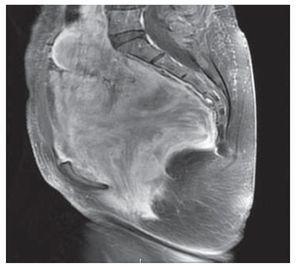

Mujer de 41 años de edad, sin antecedentes, que consultó por historia de dolor pélvico difuso, de baja intensidad, no irradiado, de ocho meses de evolución. Al examen físico se encontró una masa adherida a planos profundos y poco dolorosa a la palpación. Se le realizó una tomografía computadorizada que informó una extensa neoplasia pélvica de características malignas, que se extendía hasta el espacio isquiorectal, con desplazamiento y compresión de la vejiga y el útero, además de escaso líquido alrededor de la lesión (Figura 1). Se realizó una resonancia magnética nuclear que demostró una lesión de 14 x 14 cm, posiblemente de origen lipomatoso con degeneración mixoideangiolipomatosa, con probable infiltración al recto y sigmoides, dilatación pielo-ureteral bilateral por obstrucción del tercio distal de los uréteres (Figuras 2 y 3). Se realizó una colonoscopia que sólo evidenció desplazamiento del sigmoides por compresión extrínseca. Se le realizó una laparotomía exploratoria encontrando una masa pélvica de 15 x 20 cm, la cual se pudo separar de las estructuras adyacentes y resecar en su totalidad. El reporte histopatológico fue de una masa de 15 x 18 cm, con un peso de 260 g, de color amarillo-gris liso y opaco, de aspecto nodular y consistencia blanda. Al corte se encontraron áreas quísticas compatibles con angiomixoma (Figura 4). La paciente presentó una evolución satisfactoria, se le dio egreso. Actualmente se encuentra asintomática y sin datos de recurrencia.

Figura 2. Tomografía computadorizada que mostró masa con infiltración al recto sigmoides con obstrucción ureteral bilateral

Figura 3. Tomografía computadorizada que mostró masa con infiltración al recto sigmoides